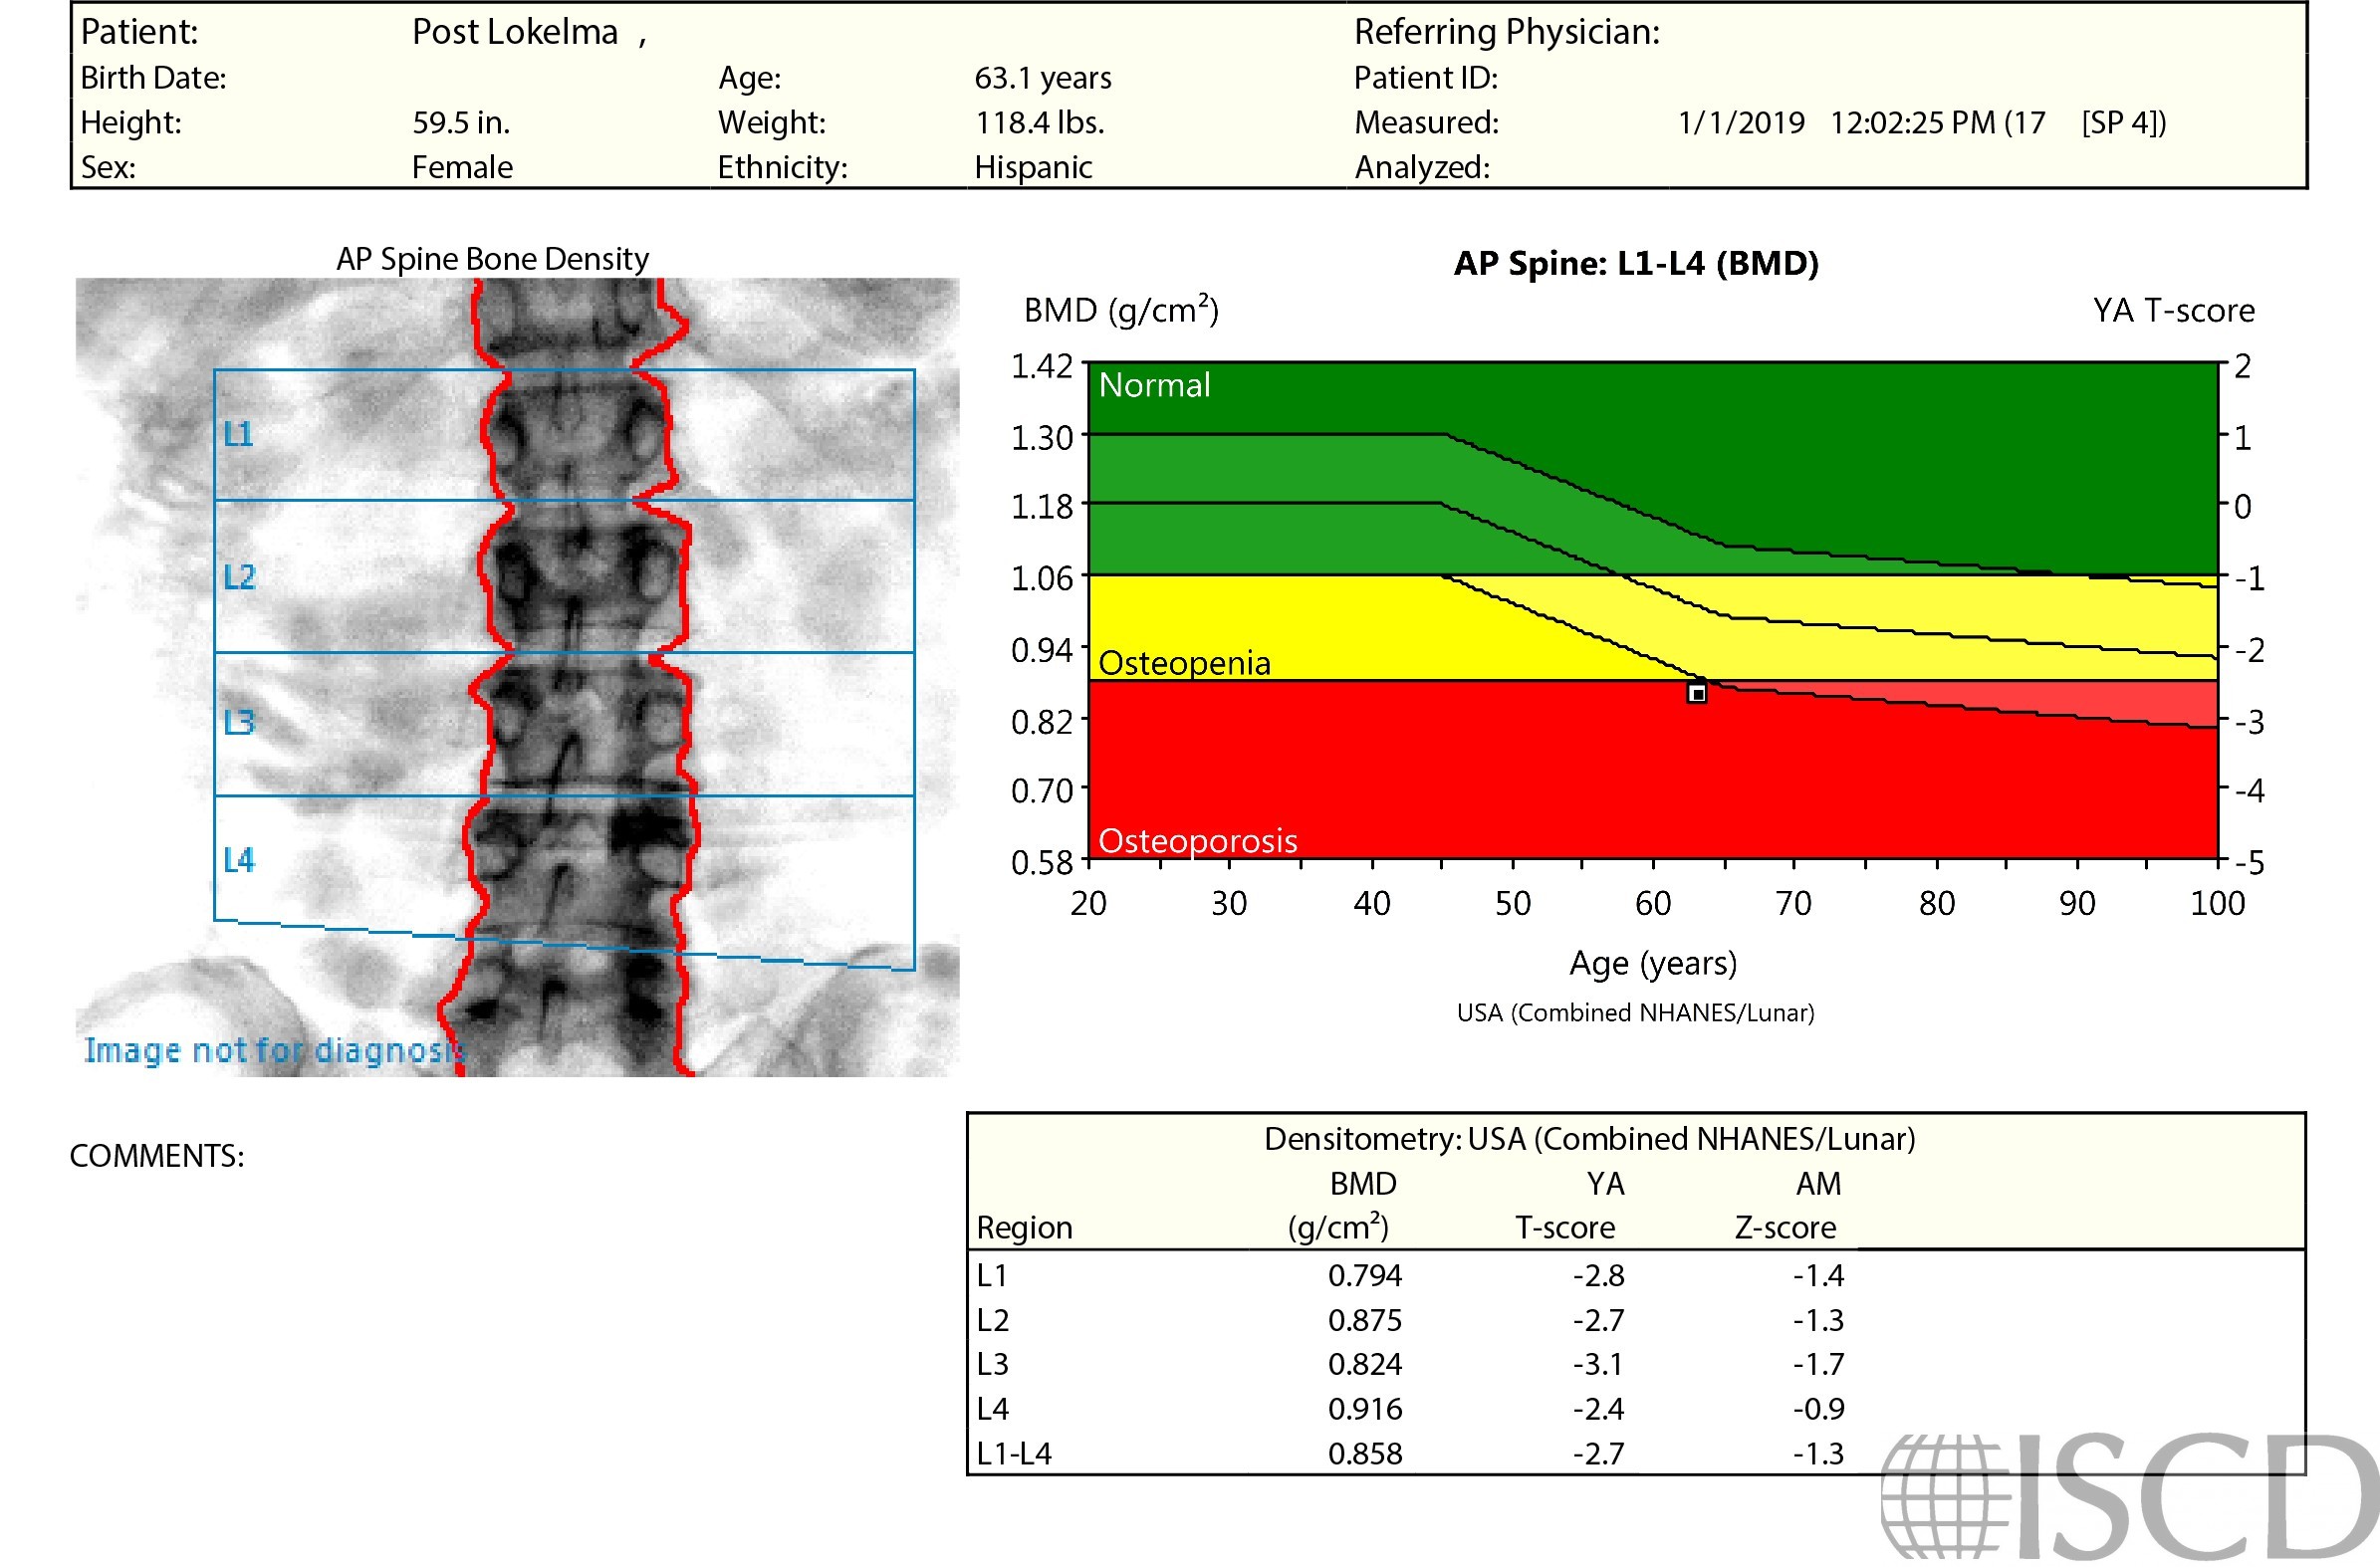

This is a patient with a baseline and follow-up scan after 2 years of Prolia. There was a visual difference between the scans, with increased and diffuse gray color on the followup spine scan. The total femur was stable at 0.639 g/sq cm at baseline and 0.631 g/sq cm at follow-up. History and further patient interview revealed that Lokelma was started between scans. Lokelma is sodium zirconium cyclosilicate and is used to treat hyperkalemia. It attracts potassium for excretion to prevent absorption. The Lokelma would affect the soft tissue baseline and thereby affect measured bone mineral density. A medication history can be very useful in evaluation of DXA scans and it is important to evaluate the images for differences between scans..